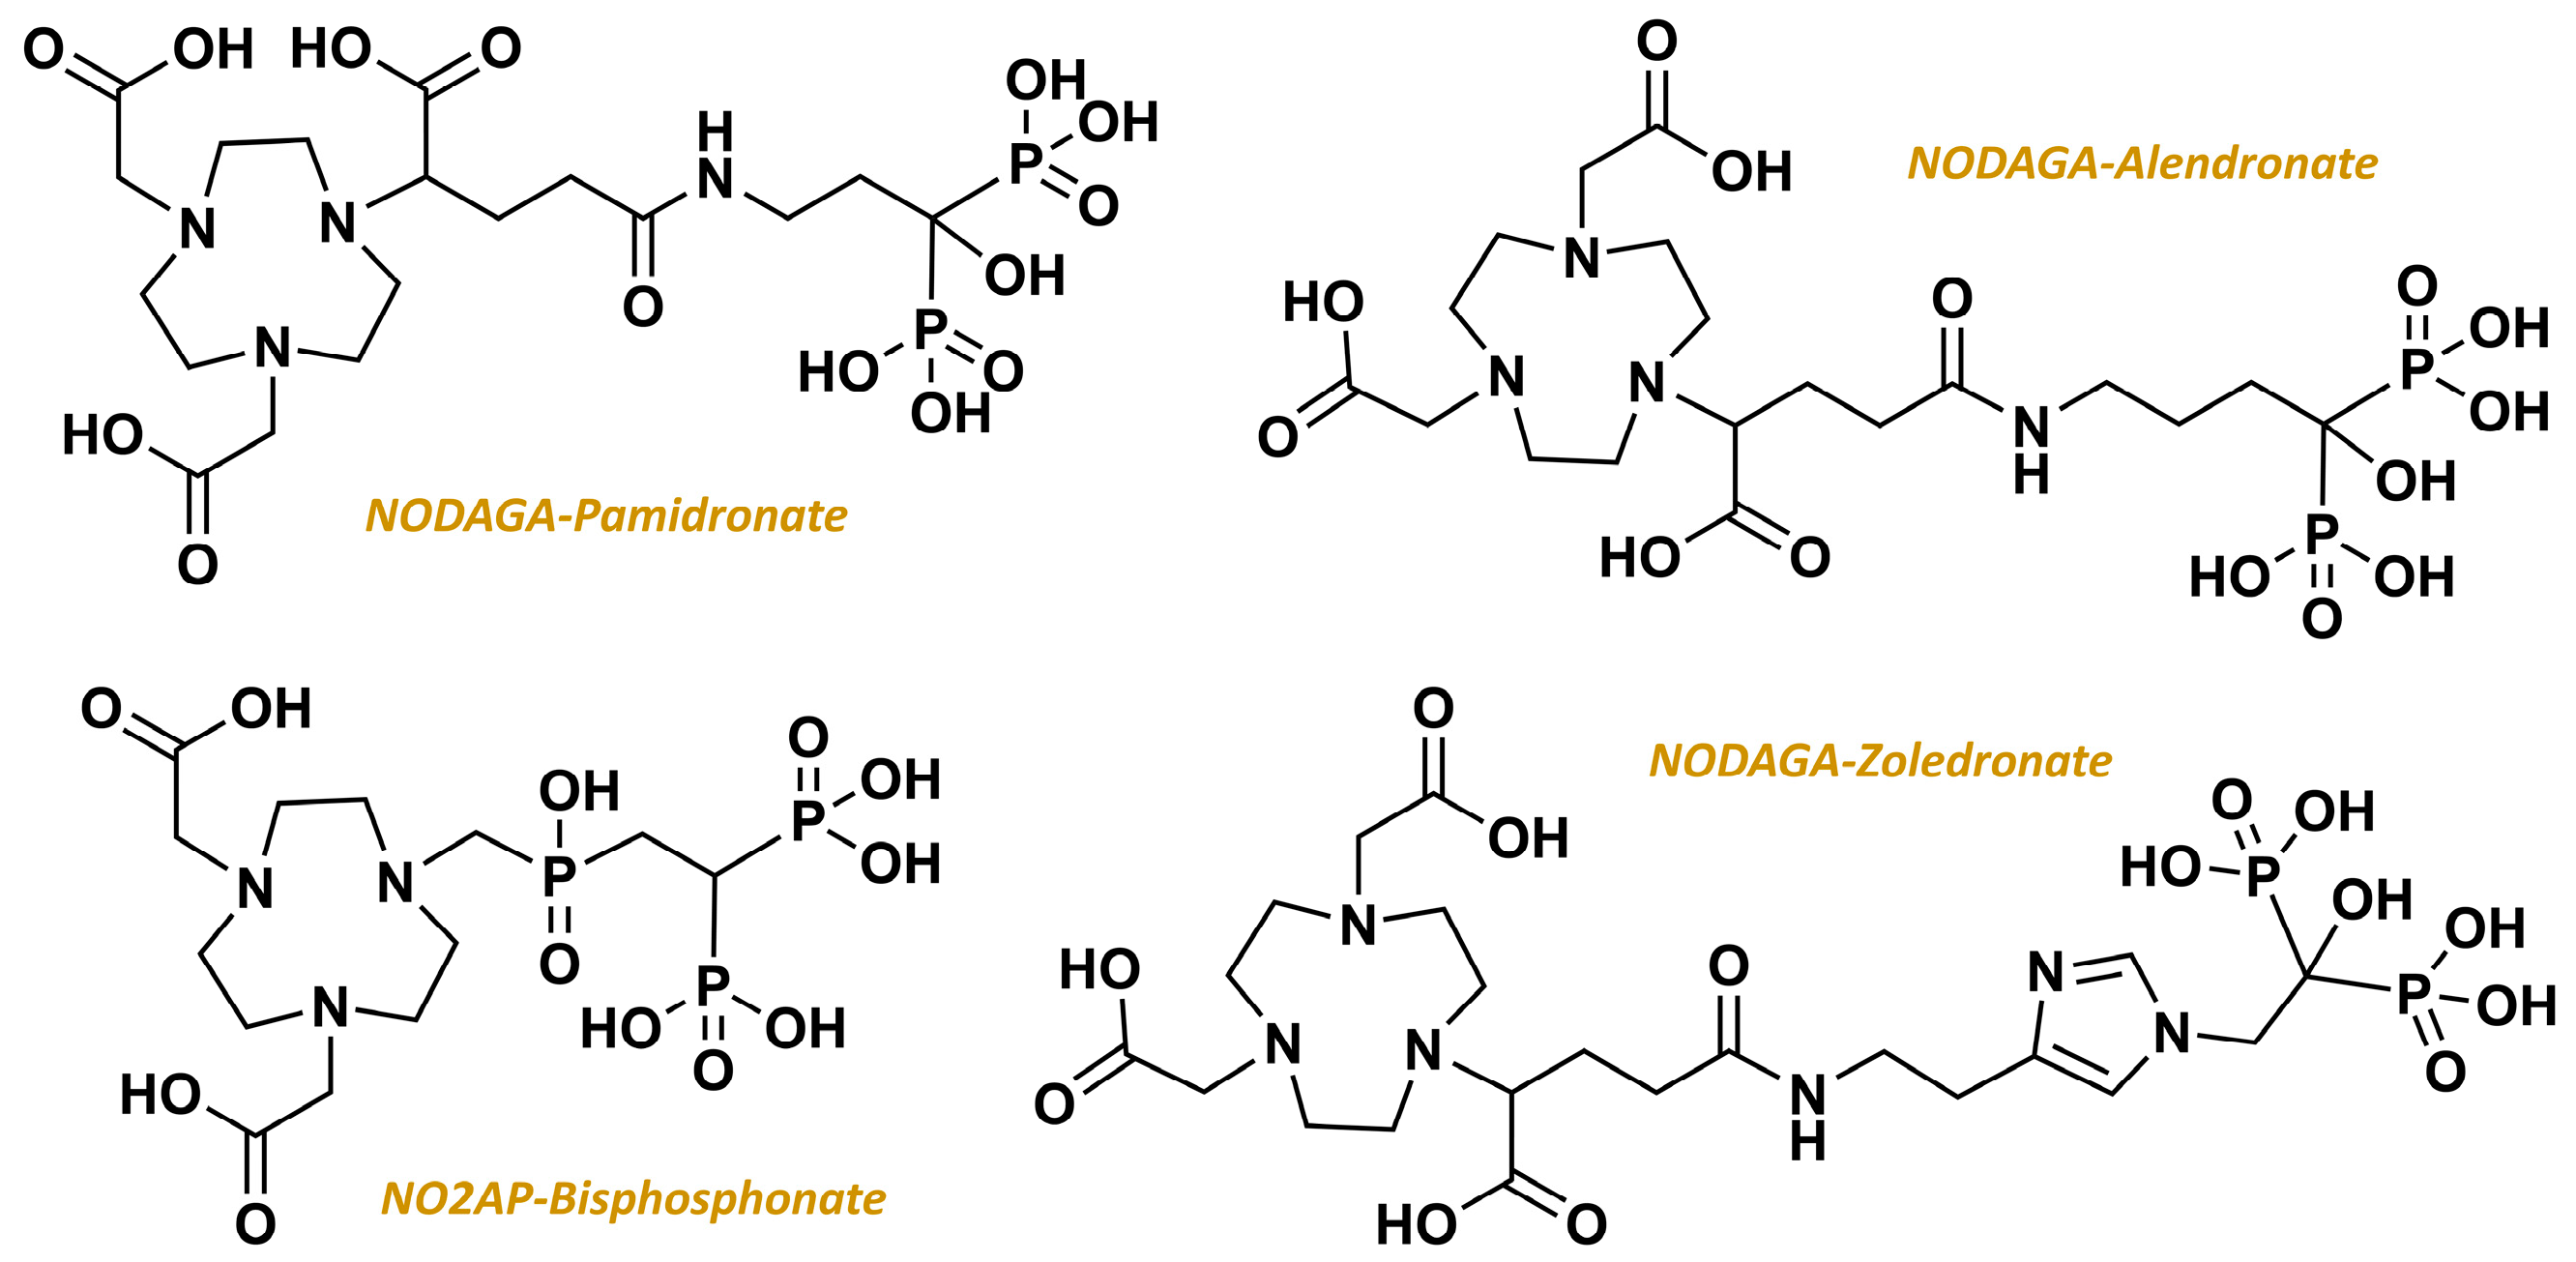

2.3. From Standard Bisphosphonates to Bifunctional Derivatives Optimized for Nuclear Medicine

- Pfannkuchen, N.; Meckel, M.; Bergmann, R.; Bachmann, M.; Bal, C.; Sathekge, M.; Mohnike, W.; Baum, R.P.; Rösch, F. Novel Radiolabeled Bisphosphonates for PET Diagnosis and Endoradiotherapy of Bone Metastases. Pharmaceuticals 2017, 10, 45. [Google Scholar] [CrossRef] [PubMed]